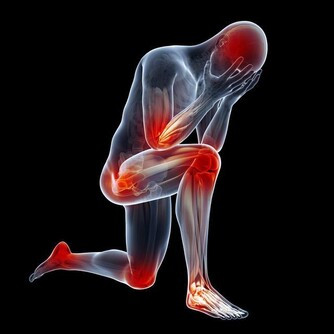

9.會引起頸椎僵硬: 久坐會影響頸動脈對頭部的供血,還破壞了正常生理彎曲,容易出現弓背或骨質增生。

10.易發生肌肉痙攣: 久坐使血流不暢,肌肉僵硬、痠痛、萎縮,使肌肉失去力量和彈性而發生痙攣。 11.會引起腰背疼痛: 久坐使得整個軀體重量全部壓在腰骶部,使腰背肌長期處於緊張狀態。